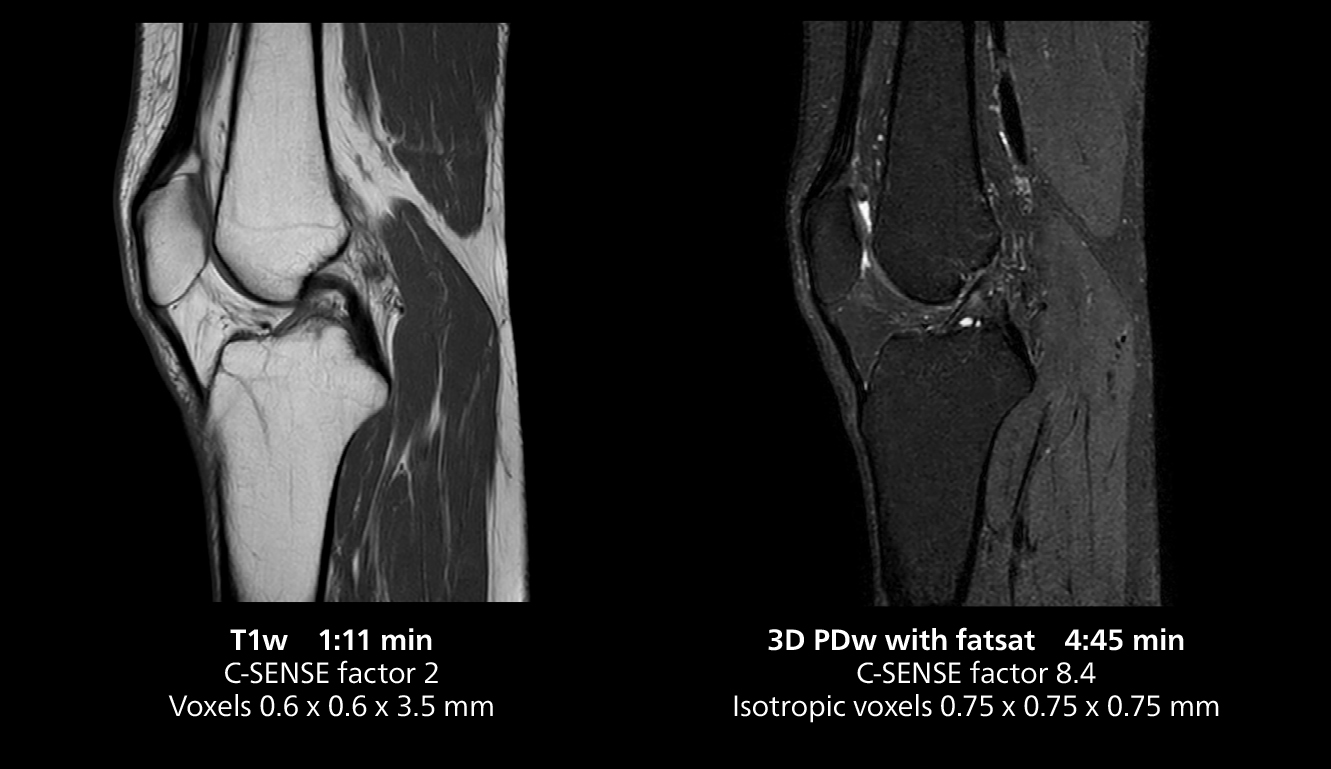

According to Dr. Gellée, the hospital conducts an average of four studies each hour, totaling about 40-45 patients per day on their MR 5300. Studies are read by approximately 50 radiologists in the Bordeaux area. Dr. Gellée is especially satisfied with the image quality of the MR system. "I obtain higher image contrast and more anatomical precision than I was used to,” she says. “When I am able to choose, I request that studies be done on this system, because I get better anatomical image quality. For example, in the knees, I can get great images of the meniscus. To me, it looks as pretty as 3T.”

The isotropic high resolution 3D sequence in this MRI case allows for reformatting to obtain other orientations with high quality. Acquired on the MR 5300 system.

The MR 5300 with Compressed SENSE is up to 50%** faster for many exams. It can provide routine exams in less than 5 minutes and whole-body exams in less than 20 minutes. Saint-Augustin has taken advantage of that speed to create highly efficient protocols. The hospital’s standard stroke protocol is just about 8 minutes, and standard ENT, prostate PIRADS staging, and endometriosis studies all clock in at just about 10 minutes.***

“We have more speed in 3D sequences,” Dr. Gellée states. “With Compressed SENSE, we can replace two or three 2D scans withone high-quality 3D scan. High quality additional orientations are then obtained by post-processing of the 3D data set, thus saving scanning time.”